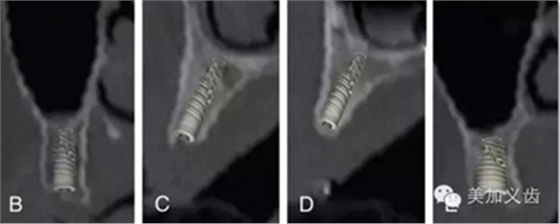

但根尖片是種植中必不可少的檢查,可以用來(lái)檢查基臺(tái)與種植體、修復(fù)體與基臺(tái)之間的密合程度,或者用于術(shù)后隨訪。

值得注意的是:使用根尖片來(lái)進(jìn)行術(shù)后隨訪,這是種植術(shù)后很重要的一件事情,而且需要定期來(lái)做,然后將拍攝出來(lái)的根尖片進(jìn)行對(duì)比,才能看到是否有骨吸收。但如果你每次拍攝的角度都不一樣,結(jié)果會(huì)讓你嚇一跳,怎么某段時(shí)間內(nèi)骨吸收這么多?!怎么某段時(shí)間骨頭又長(zhǎng)上來(lái)了?!太令人費(fèi)解了!

其實(shí)是你拍攝的角度不一樣,所得到的結(jié)果也不一樣,因此,采用平行透照技術(shù)就十分關(guān)鍵,否則你的術(shù)后回訪是沒(méi)有意義的。平行透照技術(shù)很簡(jiǎn)單,通過(guò)X線片定位器就可以做到,讓你的X線接收器和管球平行,這樣每次拍攝的角度都是一樣的了。

我們的建議是:在對(duì)患者進(jìn)行評(píng)估時(shí)要同時(shí)拍攝根尖片和曲面斷層片,在進(jìn)行手術(shù)設(shè)計(jì)時(shí)建議拍攝CBCT,在術(shù)后觀察和隨訪時(shí)可以拍攝根尖片,別忘了平行投照技術(shù)哦,這是既萬(wàn)無(wú)一失又節(jié)省成本的做法。